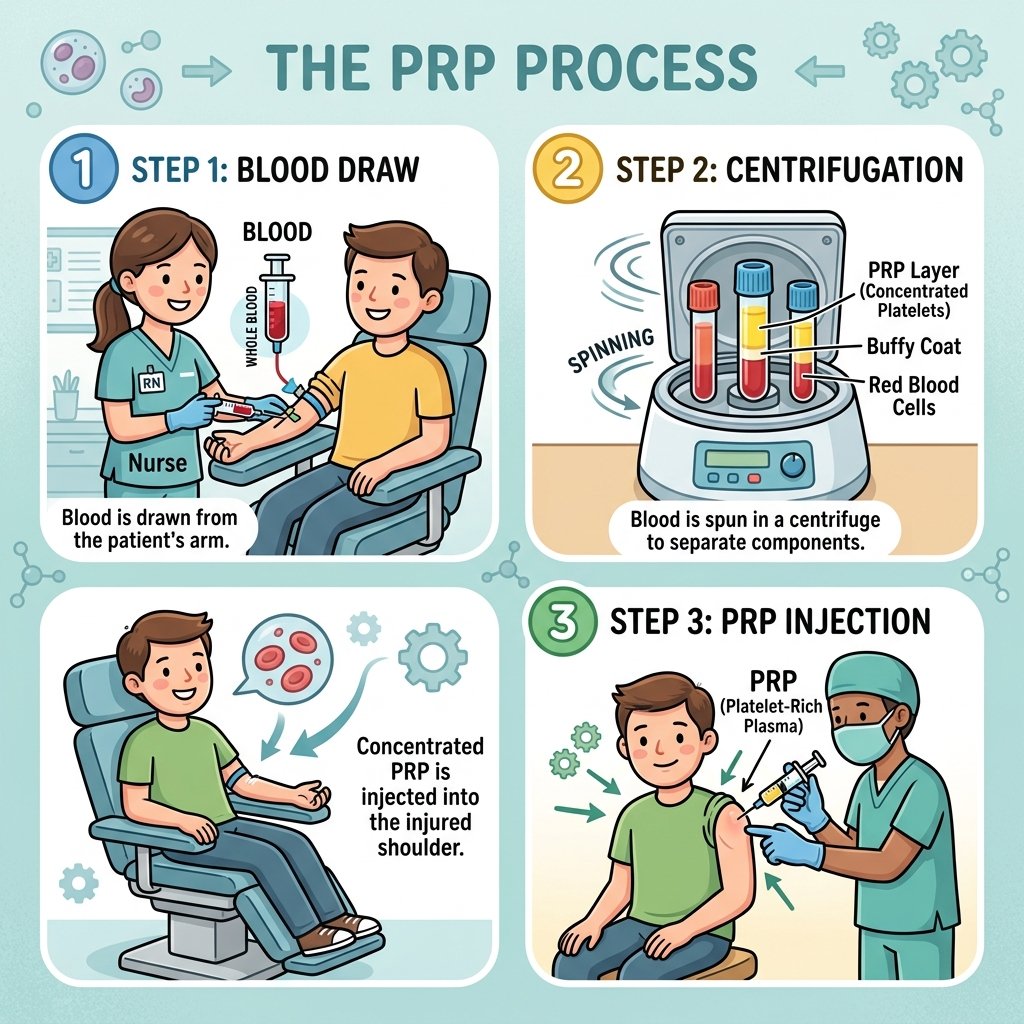

1 Essential PRP Injection Shoulder London Guide

PRP injection shoulder London clinics offer a powerful, evidence-based alternative to steroids. If you have been told you need a...